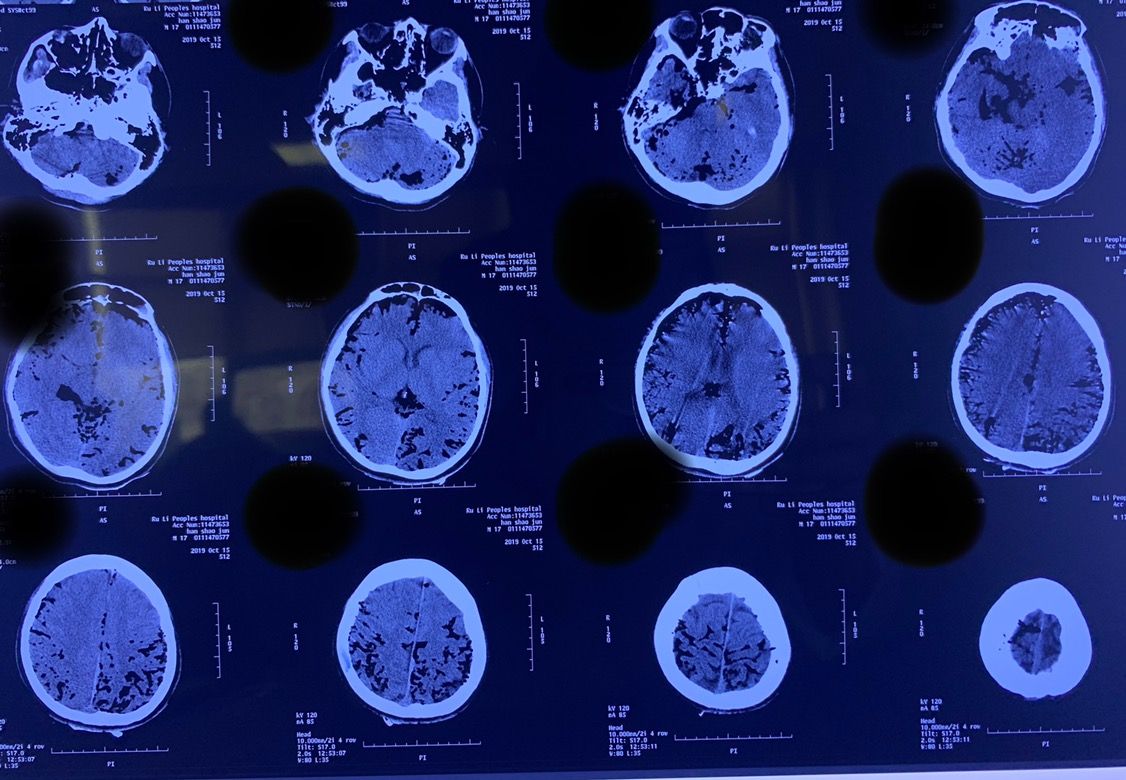

患者,Xxx,男,17岁;患者于2019年10月15日因车祸被送至当地医院救治。入院后查体:深昏迷,GCS评分4分,双侧瞳孔等大等圆,直径约3mm,光反射迟钝,疼痛刺激反应弱,生理反射存在,病理反射未引出。入院后立即给予气管插管,呼吸机辅助呼吸,并给予对症支持治疗。急诊查头颅CT示:颅内广泛积气;左枕骨骨折。

因病情危重,家属决定转院。于伤后11小时送至德宏州医院进一步治疗。患者于10月16日23时左右突发右侧瞳孔散大,急诊复查头颅CT示右侧额颞顶枕大面积脑梗死。